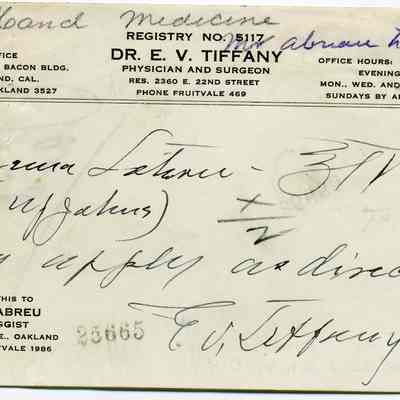

Bill Bill

Bill Bill

Bill Bill

Bill Bill

Bill Bill

Bill Bill

Bill Bill

Bill Bill

Bill Bill

Bill Bill

Bill Bill

Bill Bill

Bill Bill

Bill Bill

Bill Bill

Bill Bill

Bill Bill

Bill Bill

Bill Bill

Bill Bill

Bill Bill

Bill Bill

Bill Bill